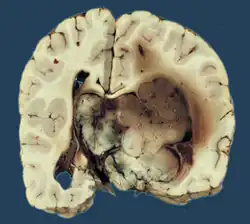

Choroid plexus papilloma, also known as papilloma of the choroid plexus, is a rare benign neuroepithelial intraventricular WHO grade I lesion found in the choroid plexus.[1] It leads to increased cerebrospinal fluid production, thus causing increased intracranial pressure and hydrocephalus.[2]

Choroid plexus papilloma occurs in the lateral ventricles of children and in the fourth ventricle of adults. This is unlike most other pediatric tumors and adult tumors, in which the locations of the tumors is reversed. In children, brain tumors are usually found in the infratentorial region and in adults, brain tumors are usually found in the supratentorial space. The relationship is reversed for choroid plexus papillomas.

Choroid plexus tumors are divided into three categories by the World Health Organization (2016):[9] papillomas (grade I), atypical tumors (grade II), and carcinomas (grade III). Less than two mitotic figures per 10 high power fields are present in CPPs, two to five are present in atypical ones, and more than five are present in carcinomas. The tumors are visible as pink, soft, spherical lumps with erratic projections and considerable vascularity.